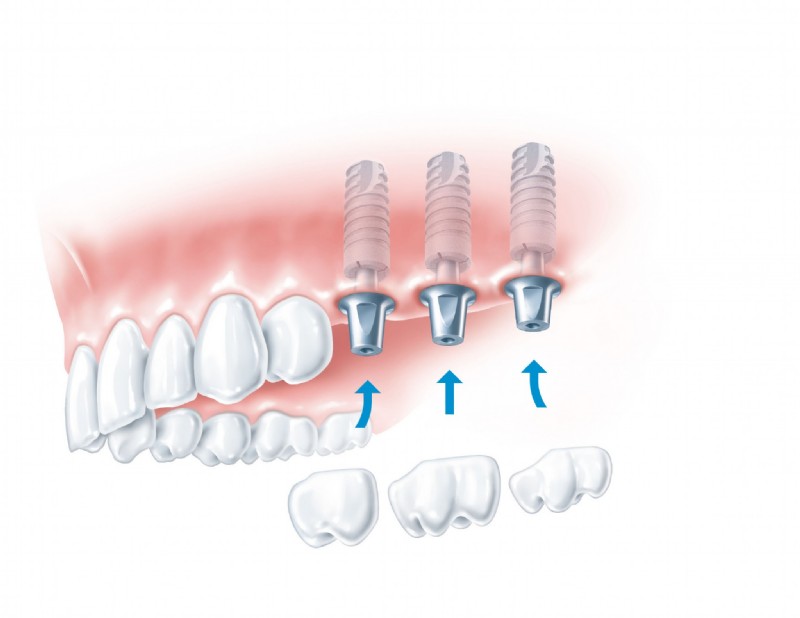

Als Spezialisten auf dem Gebiet der Implantologie wissen wir, wie man hochwertige Implantate stress- und schmerzfrei einsetzt und, wenn erforderlich, zuvor den Knochen aufbaut. Grundlegend werden in einem Beratungsgespräch all Ihre Fragen geklärt. Erst wenn Sie Vertrauen gefasst haben beginnen wir mit der professionellen Behandlung. Wir bieten Ihnen Einzelzahnimplantate, Brücken auf zwei oder mehreren Implantaten, zahnlose Kieferversorgung mit Implantaten, Brücken oder Halteelemente für Prothesen sowie maßgeschneiderte Lösungen für jedes individuelle Problem.

Hochqualitative künstliche Zahnwurzeln können natürliche Zähne sehr effektiv ersetzen. In einem ersten Schritt wird das Implantat-Bett aufbereitet, sodass das Implantat – eine Schraube aus Reintitan – problemlos in den Kiefer geschraubt werden kann. So können einzelne Zähne ersetzt oder Prothesen fixiert werden.